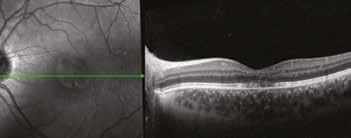

Dec. 2021 7- 8/10 0.18 logmar

Nov. 2022 8/10 0.16 logmar

Dec. 2021 10/10 0.06 logmar

Il lungo follow up del paziente durato 5 anni in assenza di cura integrativa continuativa se non saltuario uso di formula ared2 per brevi cicli mostra un significativo peggioramento anatomico strumentale OCT e funzionale del paziente con evoluzione dallo stadio 1 allo stadio II/III e solo dopo uso concomitante di DHA algale OMEGAL DHA ed un Complesso antiox si osservava una eclatante ed imprevedibile risposta, nei successivi 18 mesi in occhio sinistro e 24 mesi in OD, con completo riassorbimento del voluminoso accumulo lipofuscinico senza significativa evoluzione atrofica. Dopo inizio della cura invece si osserva un miglioramento significativo e duraturo dell’aspetto delle linee recettoriali e conseguentemente della qualità visiva in entrambi gli occhi, con un significativo miglioramento della qualità di vita del giovane paziente.

Sopra, miglioramento progressivo dopo cura.